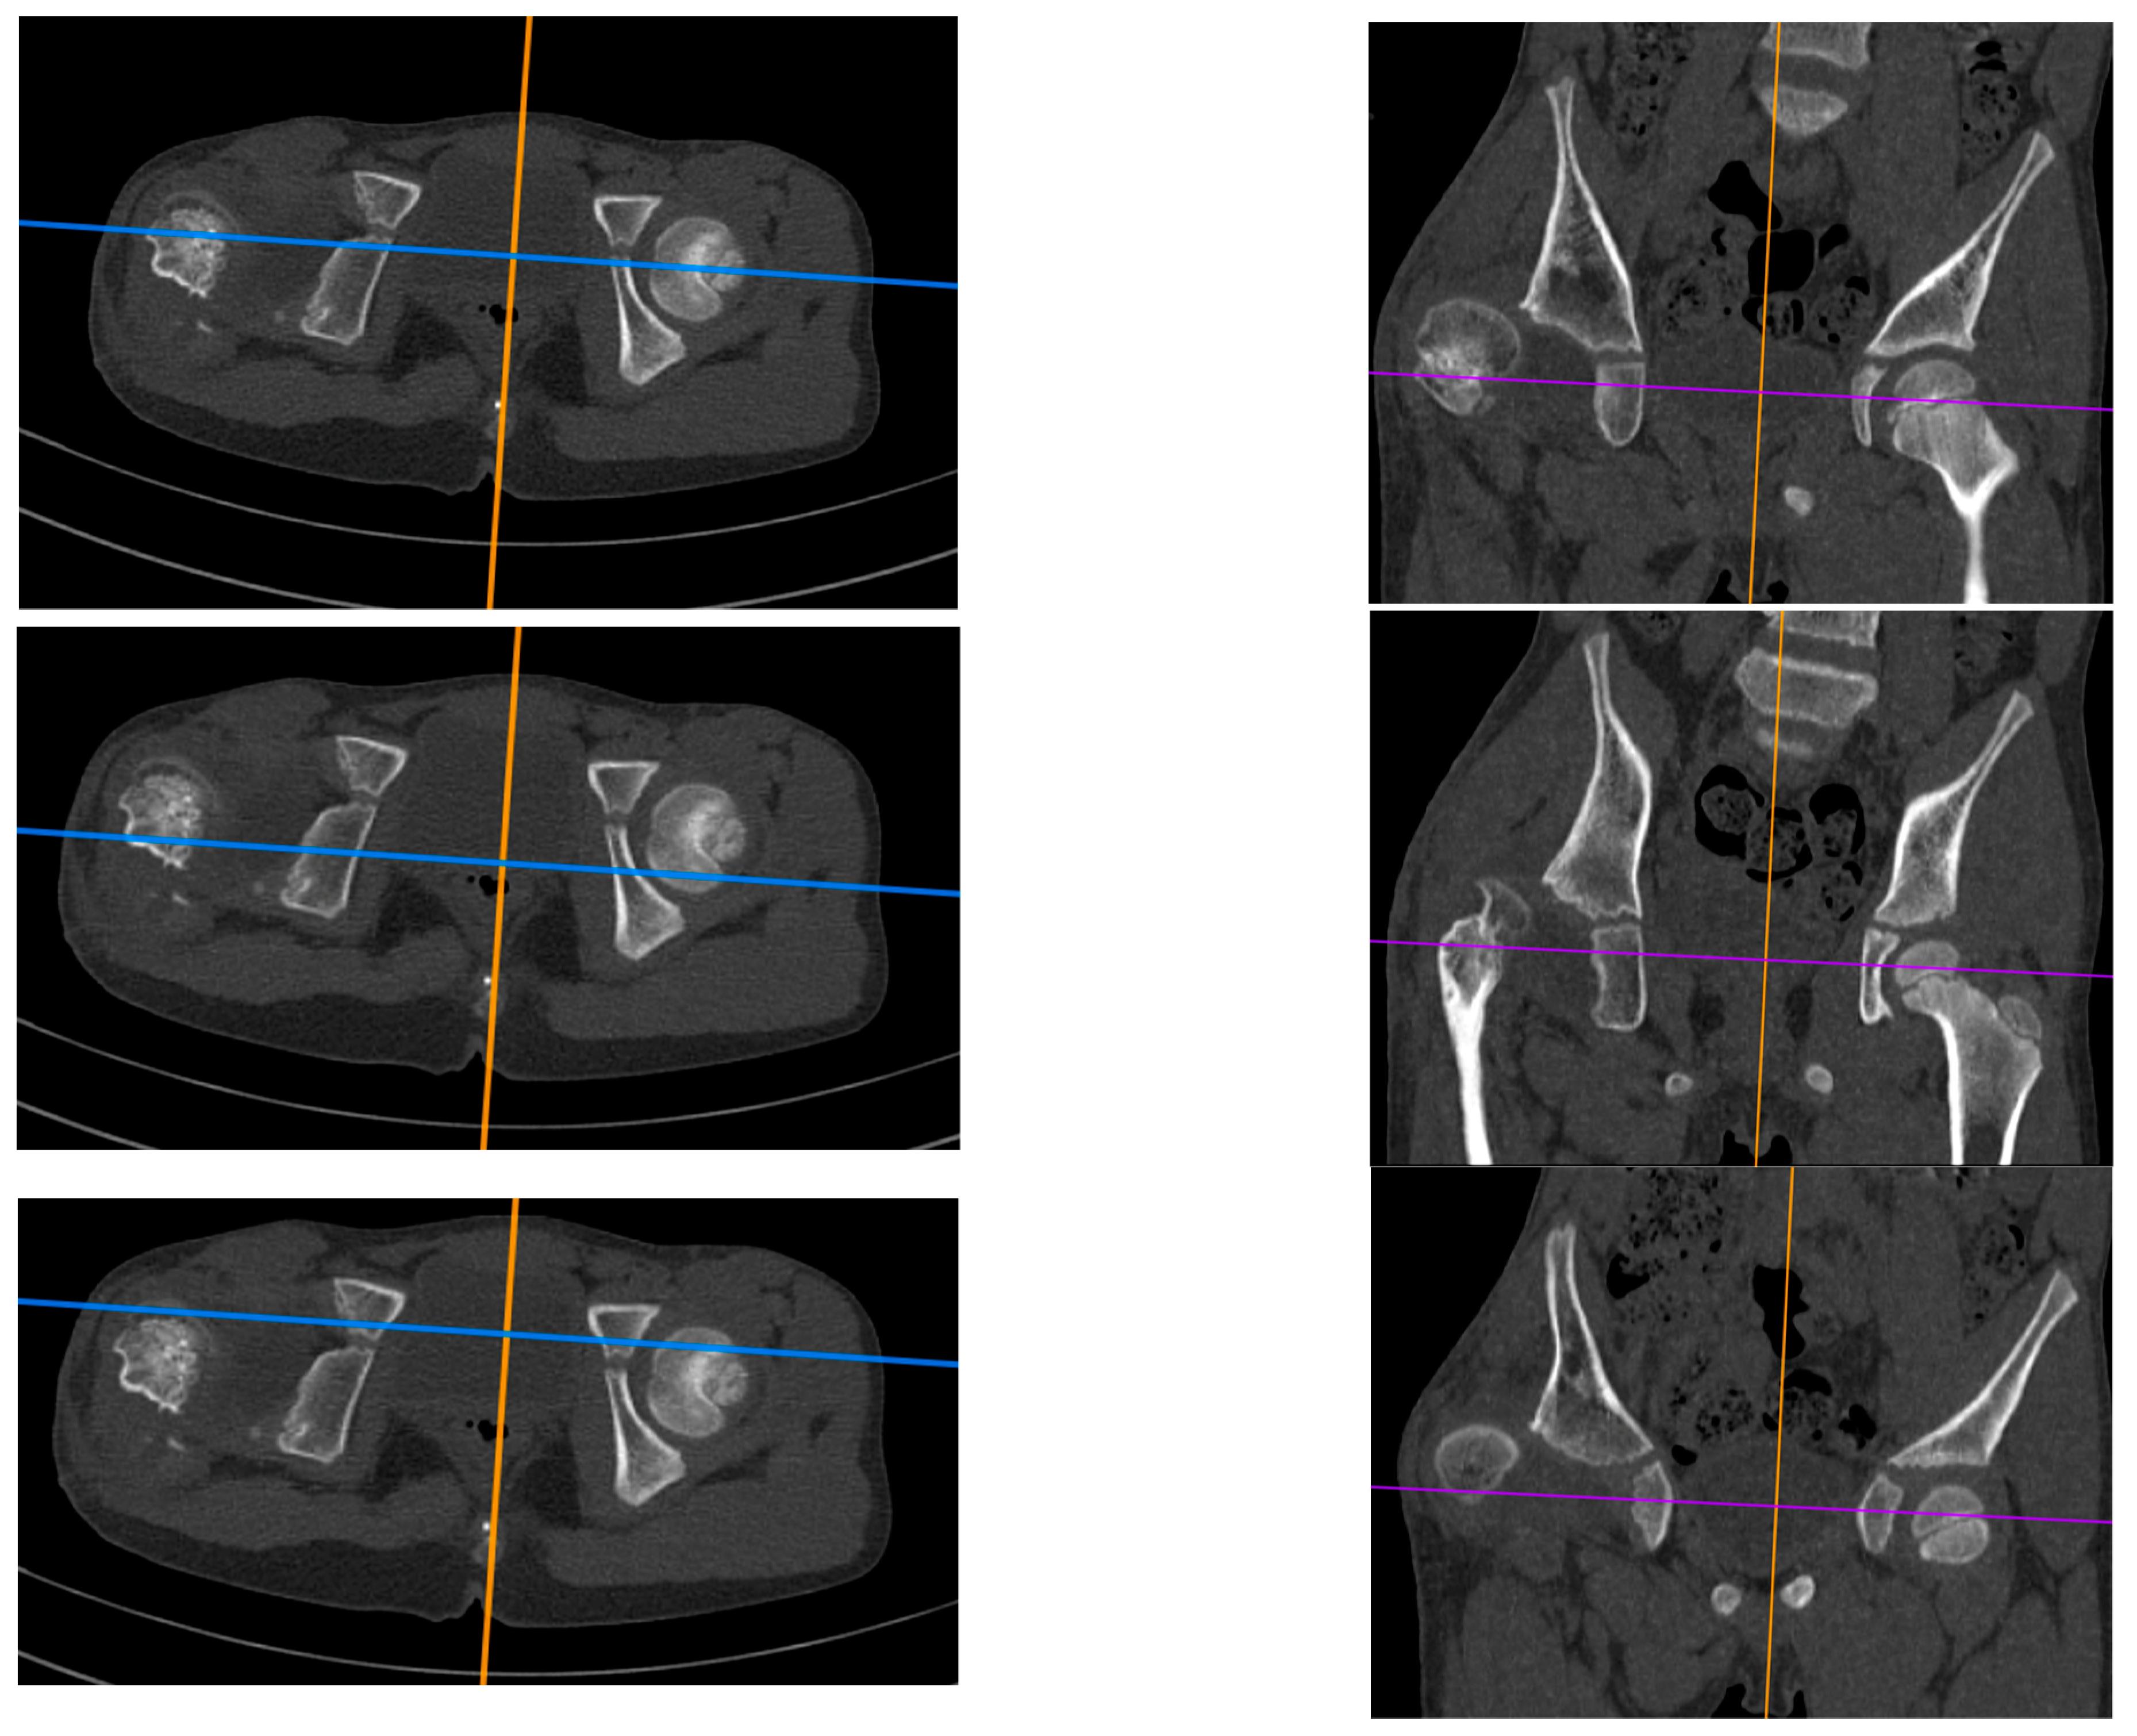

The study is a retrospective cohort review. We have reviewed medical histories and radiograms. The patients were examined three times: (1) before hip reconstruction surgery, (2) before femoral lengthening, and (3) at follow-up. The patients underwent standard AP hip joints radiograms, internal rotation hip radiograms, Rippstein position radiograms [21], and standing lower limbs AP long cassette radiograms. We have measured the Center-Edge Angle (CEA, Wiberg), the Acetabular Inclination (AI), the Neck-Shaft Angle (NSA), and the Antetorsion Angle (AT), and the Shenton line was also evaluated [22,23,24,25,26,27]. Femoral torsion normal values were adapted from the Tönnis study [23], femoral retrotorsion was accepted as a negative true AT value, and diminished AT was accepted as <20 deg. Computed Tomography (CT) scans were available in all 6 patients with hip instability. The following parameters were measured on CT scans [18,28,29,30]: Acetabular Anteversion (AA), Axial Acetabular Index (AAI), and Acetabular Inclination in the anterior (AIa), middle (AIm), and posterior (AIp) part of the acetabulum. CT scans with plane presentation and measurements are shown in Figure 2 and Figure 3. Statistical analysis was performed with the use of STATISTICA v13.3 and PQStat v1.8.4. Significance was determined as p < 0.05.

Figure 2.

CT examination of patient with right hip dislocation. Left: transverse view, right: coronal view. Evaluation of medial (first row), posterior (middle row), and anterior (last row) parts of the acetabulum.

Figure 3.

CT scan showing AIm measurements (left): 24 deg on the affected side vs. 6 deg on the healthy side. Hip radiogram of the same patient with hip joint dislocation (right).